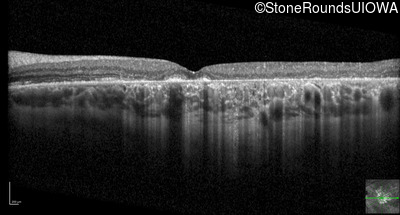

Optical Coherence Tomography - Right - 20/125 -2

Exemplar / OCT Stack

OCT Stack